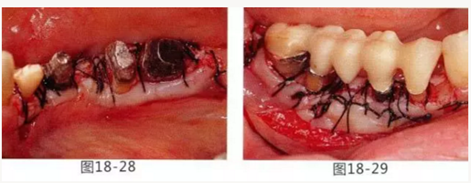

圖18-28 同部位的舌側照片。角化牙齦向根尖側移動。

圖18-29 佩戴臨時橋體。

圖18-30 在頰側以及舌側涂上牙周塞治劑。然后將咬合面少許削除。

圖18-31 手術完成1周的頰側面照。

圖18-32 同部位的舌側面照。